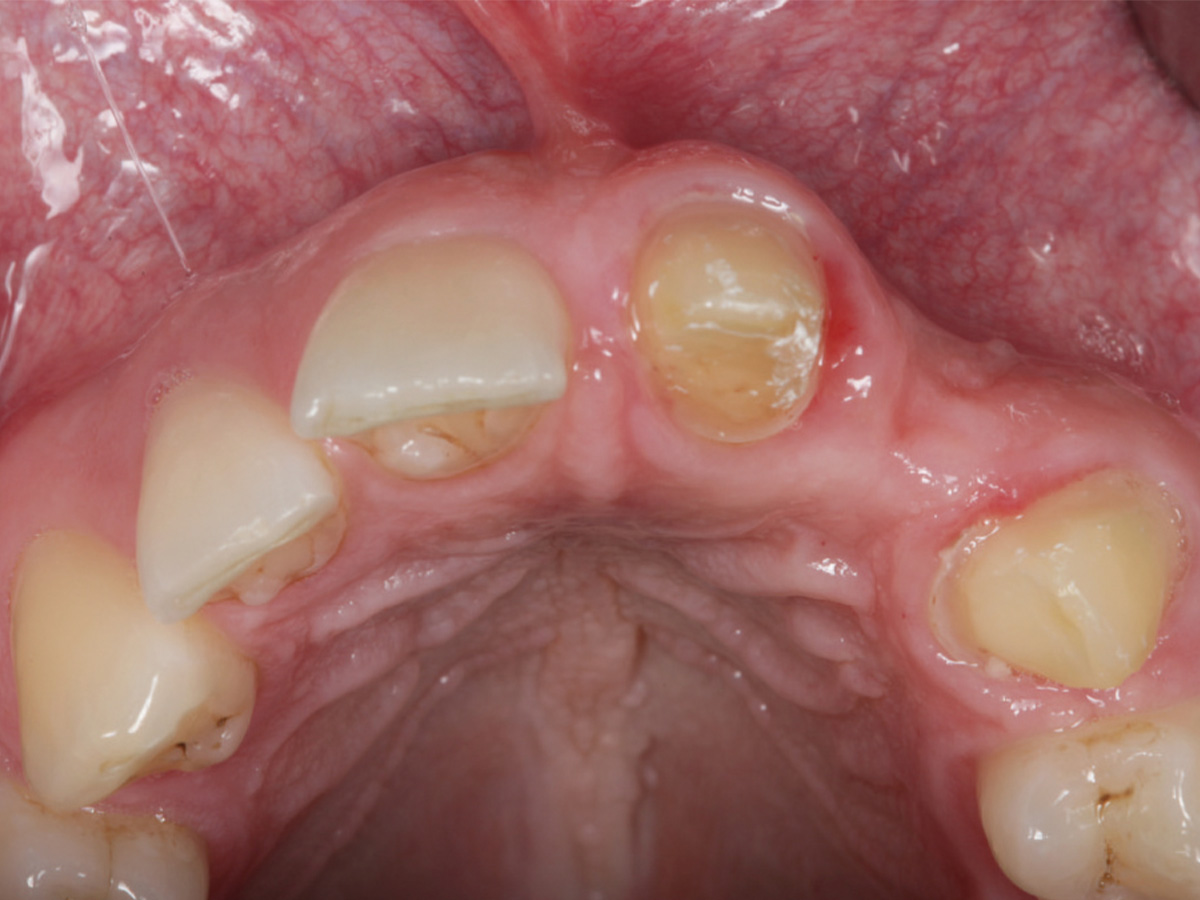

Abbildung 1

Horizontaler Alveolarkammdefekt, Einzelzahnimplantat soll eingesetzt werden.